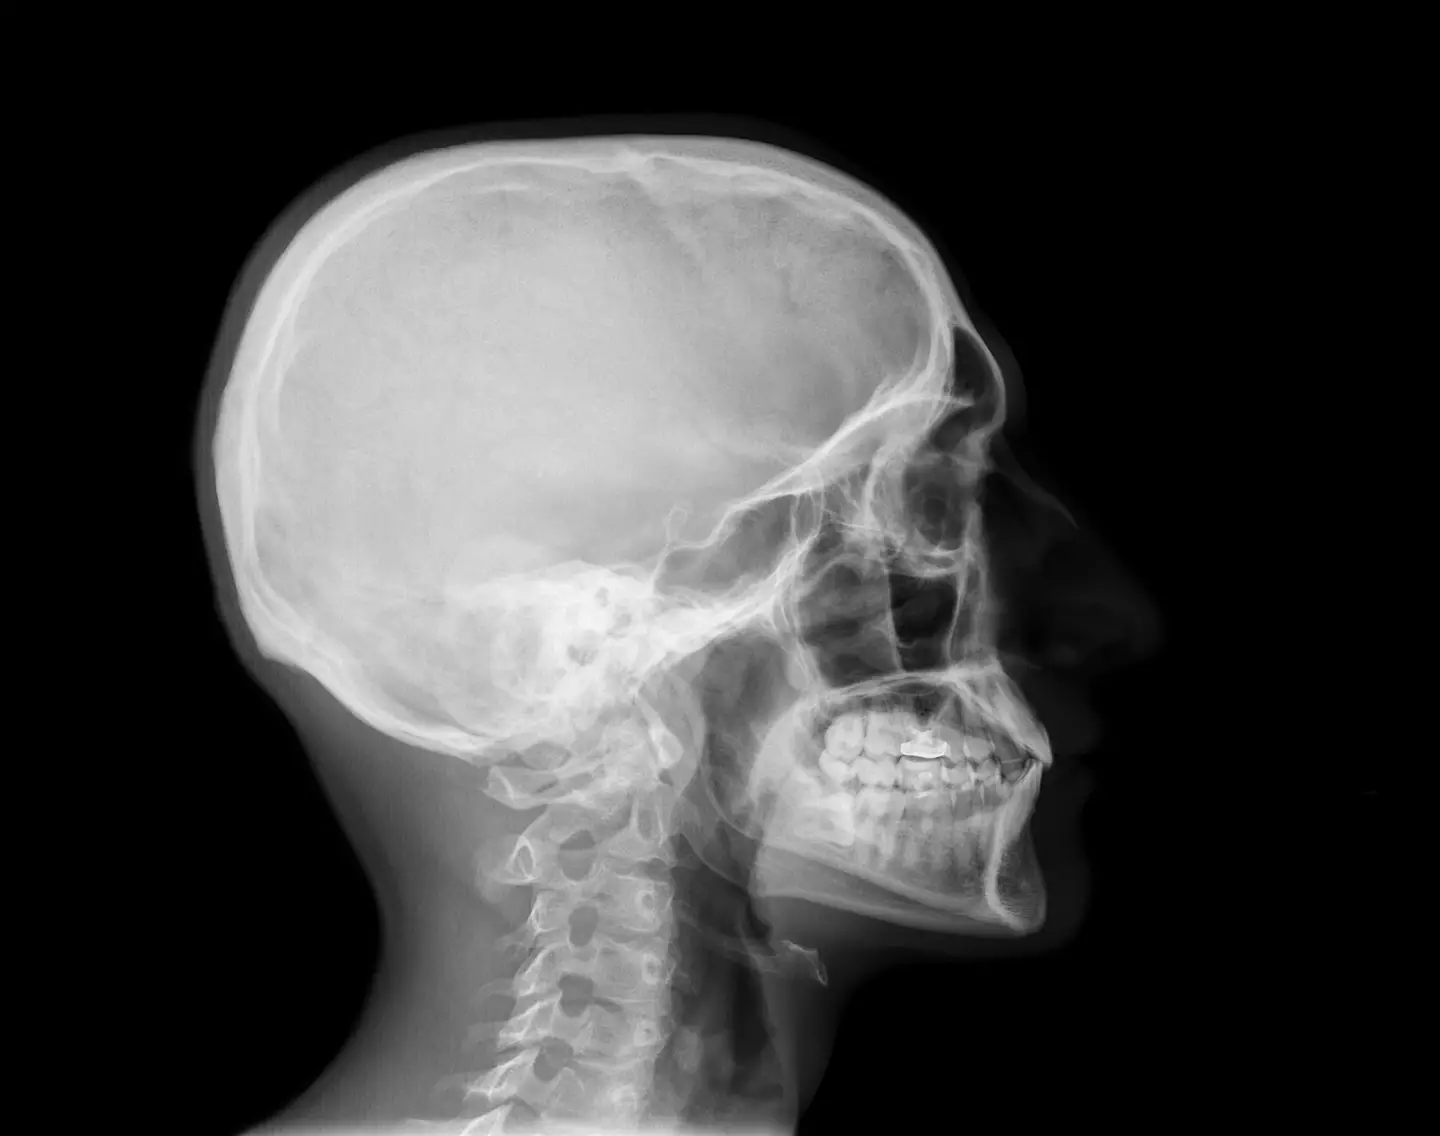

It turns out that the chin isn't entirely what you might have thought as lots of animals have a lower jawbone, the mandible, but that doesn't mean they have a chin.

The chin is only present on a human mandible and it refers to a little bit of bone jutting out of the front which pokes forward.

No other species in the world that we've yet discovered has got one of those little jutting nubs of bone on their jaw, so they don't get entry to the chin club.